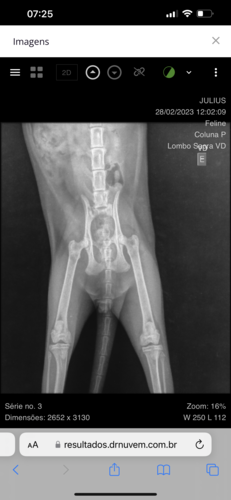

Vakinha Para Ajudar um pobre gato que foi abandonado na rua com tumor na Região Coluna sacral.

haverá mais gastos para exames, mais medicamento, possíveis cirurgias e etc. Como não posso arcar mais com essas despesas, preciso de ajuda para dar continuidade o tratamento do gatinho.